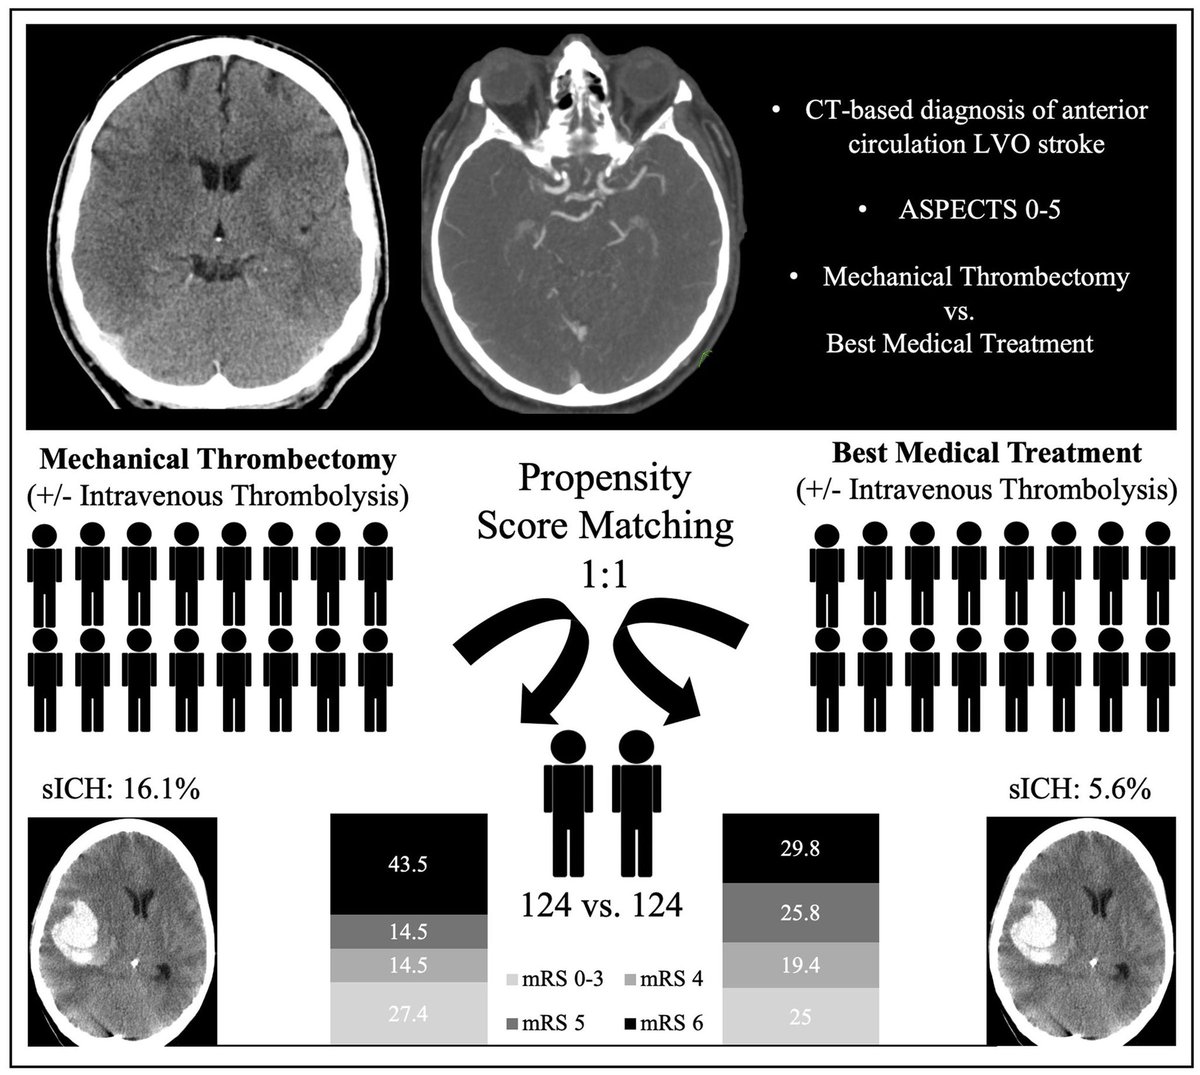

@AshuPJadhav

Thrombectomy in Extensive Stroke May Not Be Beneficial and Is Associated With Increased Risk for Hemorrhage https://t.co/oRDXuP0ZS1